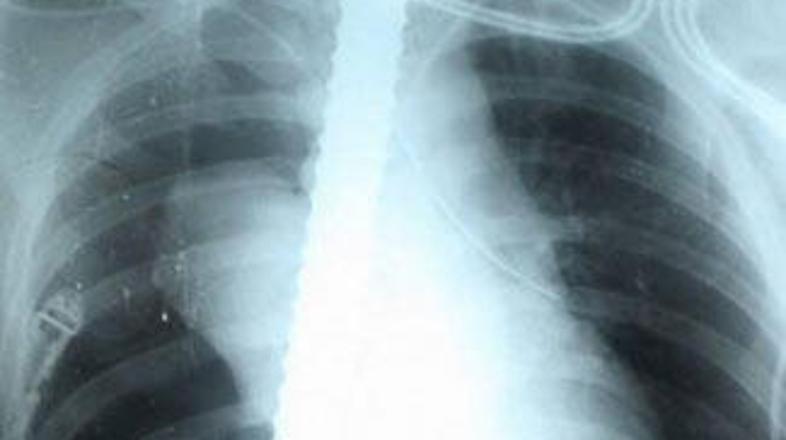

Ruski gradbeni delavec Nikolas Kolesničenko je z dveh metrov padel na železno palico, debelo 2 cm, in na njej preboden z glavo navzdol visel pet ur. Kirurgi so mu palico uspešno odstranili.

Ob prihodu na mesto nesreče so zdravniki menili, da je Nikolas zagotovo mrtev. Na njihovo presenečenje pa so mu izmerili krvni pritisk, ki je bil takšen, kot pri zdravem človeku. Dežurna zdravnica si je morala celo prižgati cigareto, da se je umirila, saj ni mogla verjeti, da je še vedno živ. Takoj so ga odpeljali v bolnišnico, kjer sta ga dve ekipi kirurgov operirali tri ure.

Palica gradbenemu delavcu na srečo ni poškodovala nobenega pomembnega notranjega organa. "Ni mi jasno, kako sem sploh padel nanjo. Zadnje, kar se spominjam, je, da sem hotel prijatelju nekaj povedati. Potem sem padel. Nato pa sem se zbudil v bolnišnici," se spominja Nikolas.

Po prvi operaciji je moral Nikolas še na drugo, saj mu je med bivanjem v bolnišnici iz ust začela teči kri. Med operacijo je bil že klinično mrtev, a je zdravnikom uspelo, da so ga vrnili med žive.

Železno palico, ki so jo izvlekli skozi vrat, so v bolnišnici spravili kot spomin na bizaren dogodek, Nikolas pa je po nesreči prenehal delati kot gradbeni delavec in je raje postal varnostnik.